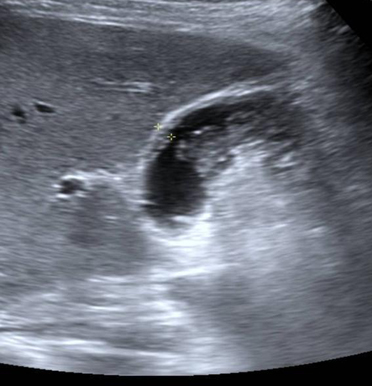

Epaissisement de la

paroi vesiculaire > 3mm , la contenue est irregulie

et image de calcul de infundibulum vesiculaire

. Cholecystite aigue lithiasique |